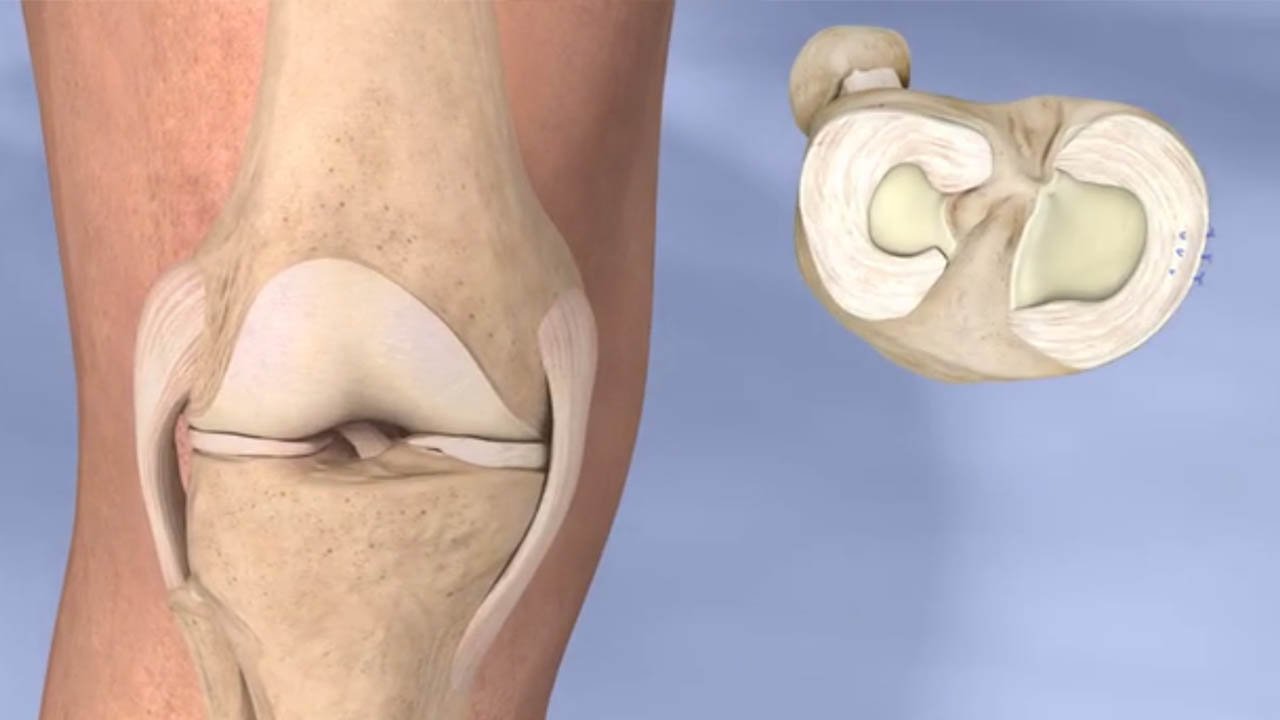

- Arthroscopic meniscus repair

- Unicondylar knee replacement

- Arthroscopic meniscus repair

- Unicondylar knee replacement